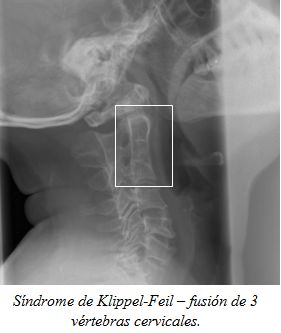

En condiciones asociadas con subluxación atlantoaxial, (por ejemplo, síndrome de Down, síndrome de Morquio, el síndrome de Larsen, y el síndrome de Marfan), se debe hacer radiografías de la columna cervical.